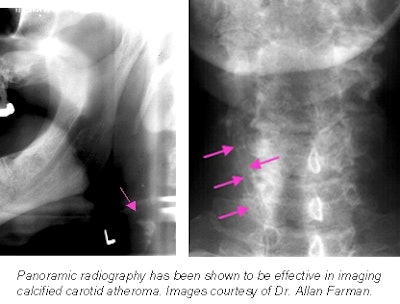

SALT LAKE CITY - Panoramic radiography isn't just for dental offices anymore; it's being used in hospital emergency rooms to evaluate possible mandibular fractures. As part of the ER complement of modalities, panoramic radiography needs to be digital (to integrate into a PACS) and it needs to be fast.

Dr. Allan Farman, professor of radiology and imaging sciences in the department of surgical and hospital dentistry at the University of Louisville in Louisville, KY, presented the results of a head-to-head comparison between charge-coupled device (CCD), storage phosphor, and film-based panoramic radiography at SCAR on Friday.